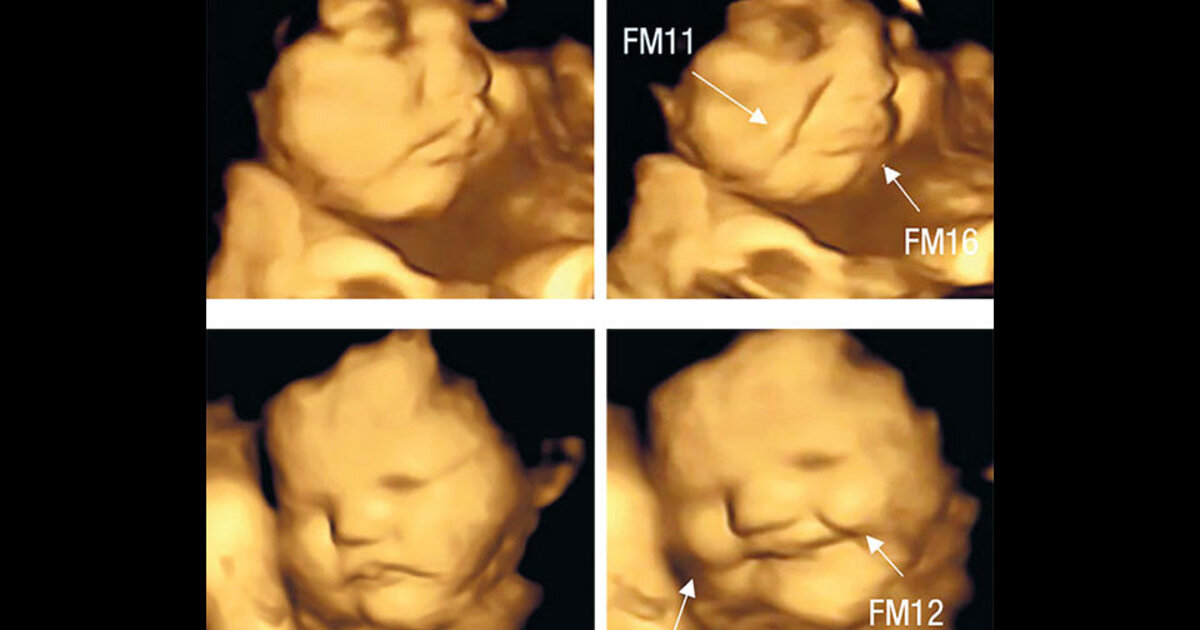

Οι ερευνητές του βρετανικού πανεπιστημίου έλαβαν τρισδιάστατες υπερηχογραφικές απεικονίσεις από 110 εγκύους, ηλικίας 18 έως 40 ετών, που βρίσκονταν στην 32η και 36η εβδομάδα της εγκυμοσύνης τους. Οι εξετάσεις πραγματοποιήθηκαν περίπου 20 λεπτά αφού οι γυναίκες είχαν καταναλώσει ταμπλέτες που περιείχαν σκόνη καρότου ή λαχανίδας (κέιλ), ενώ τους είχε ζητηθεί να μην καταναλώσουν οτιδήποτε άλλο τουλάχιστον μία ώρα πριν από την εξέταση.

Αναλύοντας τις εικόνες, οι ερευνητές είδαν ότι τα έμβρυα, οι μητέρες των οποίων είχαν φάει καρότο, έμοιαζαν να χαμογελούν ευχαριστημένα. Αντιθέτως τα έμβρυα των γυναικών που είχαν καταναλώσει τα χάπια λαχανίδας έμοιαζαν να κλαίνε ή τουλάχιστον να κάνουν μορφασμούς δυσαρέσκειας. Συγκρίνοντας τα υπερηχογραφήματα με αυτά που έλαβαν από μία ομάδα ελέγχου στην οποία οι γυναίκες δεν είχαν καταναλώσει τρόφιμα, οι ερευνητές κατέληξαν ότι η πρόσληψη κάποιας γεύσης από την έγκυο αρκούσε για να πυροδοτήσει την αντίδραση του εμβρύου.